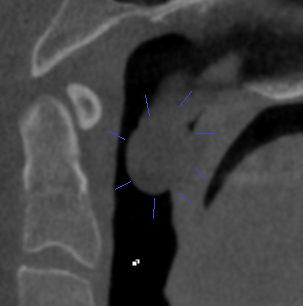

Case 3: Patient concern with breathing issues. A large mass was discovered behind the soft palate. It could not be visualized in the mouth. It was surgically removed and biopsied as benign with no further concerns.

Case 5: New patient (5 yrs old) fell off bike. Did not complain of unusual discomfort. Imaging found significant condylar (jaw) fractures on both sides of the jaw. Referral to oral surgeon was made.